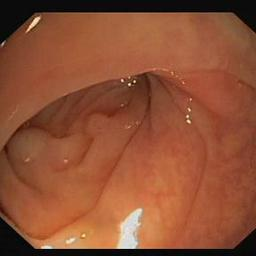

Medical image segmentation is a primary task in many applications, and the accuracy of the segmentation is a necessity. Recently, many deep learning networks derived from U-Net have been extensively used and have achieved notable results. To further improve and refine the performance of U-Net, parallel decoders along with mask prediction decoder have been carried out and have shown significant improvement with additional advantages. In our work, we utilize the advantages of using a combination of contour and distance map as regularizers. In turn, we propose a novel architecture Psi-Net with a single encoder and three parallel decoders, one decoder to learn the mask and other two to learn the auxiliary tasks of contour detection and distance map estimation. The learning of these auxiliary tasks helps in capturing the shape and boundary. We also propose a new joint loss function for the proposed architecture. The loss function consists of a weighted combination of Negative likelihood and Mean Square Error loss. We have used two publicly available datasets: 1) Origa dataset for the task of optic cup and disc segmentation and 2) Endovis segment dataset for the task of polyp segmentation to evaluate our model. We have conducted extensive experiments using our network to show our model gives better results in terms of segmentation, boundary and shape metrics.